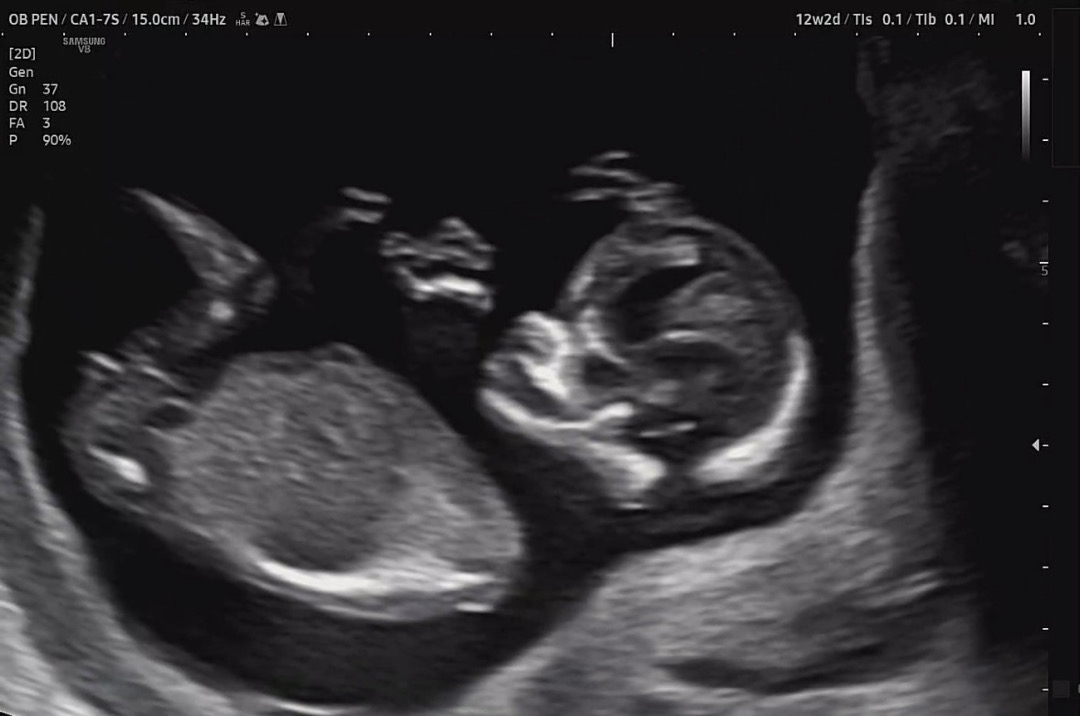

12주 각도법 한번 봐주실래요?

각도법을 잘 볼 줄 몰라서.. 도와주세요~~! 아들인가요 딸인가요??